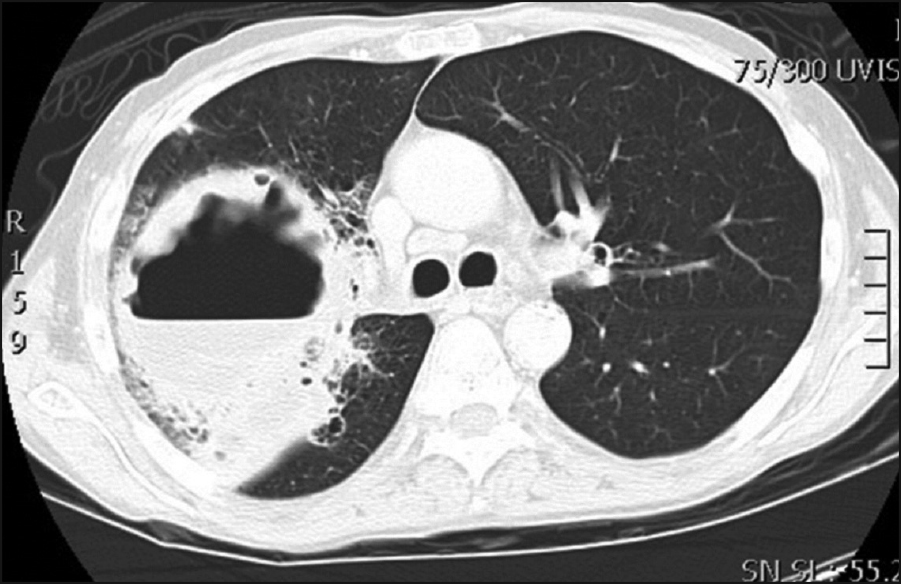

Figure 2. A CT chest with contrast showed a 13x10x12cm cavitating lesion predominantly in the right upper lobe

Figure 2. A CT chest with contrast showed a 13x10x12cm cavitating lesion predominantly in the right upper lobe(click to enlarge)

A CT chest with contrast was performed which showed a 13x10x12cm cavitating lesion with a large air/fluid level predominantly in the right upper lobe (see Figure 2). Associated with it, there was prominent reactive adenopathy in the superior, anterior mediastinum, as well as in the subcarinal position (see Figure 2).

A CT-guided biopsy confirmed a methicillin-resistant Staphylococcus aureus-positive lung cavitation, most likely secondary to his poor dentition. A full dental clearance was performed, and he was treated with a course of intravenous vancomycin and oral clindamycin with good effect.